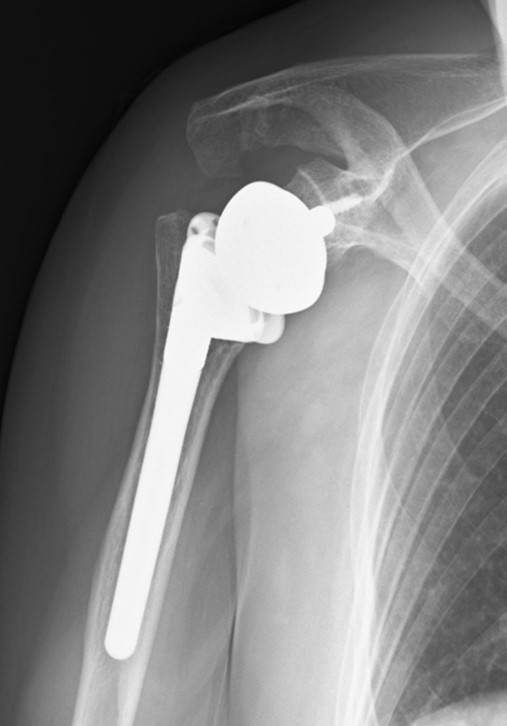

手術療法は大きく分けて人工関節置換術と関節形成術があります。軟骨が消失して変形をきたした関節に対しては人工膝関節、股関節、足関節、肩関節(リバース型を含む)、肘関節、指関節置換術を行っております。当院では感染予防のため最高ランクのクリーンルームで人工関節を行っています。

リバース型人工肩関節は2014年に本邦に導入され、腱板が断裂していても三角筋力で挙上、外転が可能になる機種であり、関節破壊と腱板断裂の両者をきたしやすいリウマチ肩にとっては朗報になっています。永瀬らはリウマチ肩に対するリバース型人工肩関節置換術の中期成績を本邦で初めて英語論文で報告しました。昨今までリウマチ肩に対していい治療法がないと言われてきておりましたが、医療従事者、患者さん双方にとって光明が見えてきており、関節鏡下手術も含め、リウマチ肩の治療方法について情報発信をしております。

下図は連結していない機種を用いた人工肘関節であり、骨切除量が少ない利点があります。